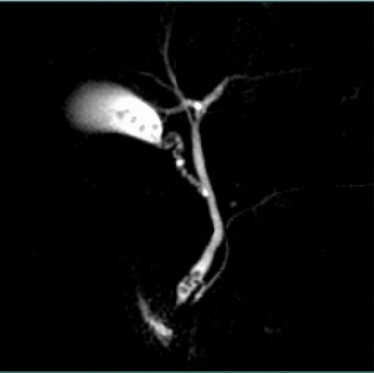

⭐ Clinical Pearl: Contrast enhancement timing is critical for diagnostic accuracy. Arterial phase imaging at 25-35 seconds post-injection captures hypervascular tumors (hepatocellular carcinoma shows 85% sensitivity), while portal venous phase at 65-75 seconds optimizes liver metastasis detection (sensitivity 90%). Delayed phases at 3-5 minutes reveal transitional cell carcinomas in the collecting system.